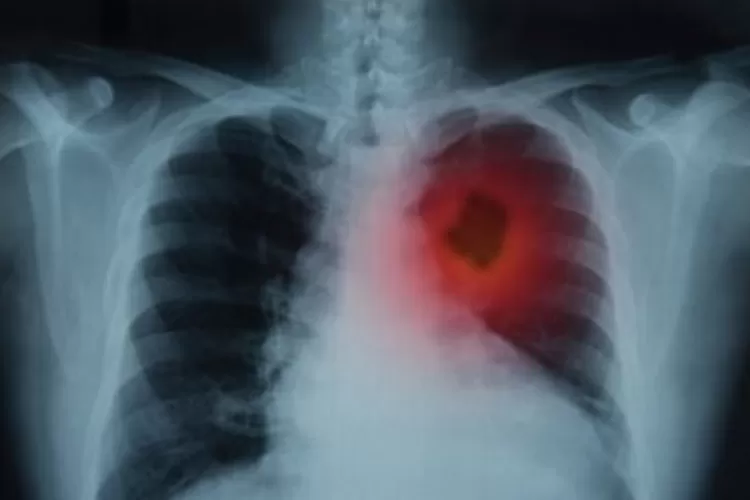

Ilustrasi kanker paru-paru. (ANTARA/Shutterstock)